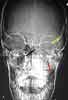

1. Eyelid swelling and discharge: The radiographsdemonstrate opacity of the ethmoid air cells on the left(A and B, black arrows) with increased opacity of theleft maxillary antrum, which is best seen on the frontalview (A, red arrow). The sphenoid and frontal sinusesare unremarkable. The increased density seen on thefilms results from the filling of the normally aeratedsinuses with opaque material (in this case, mucus).

Close inspection also reveals increased density ofthe left orbit (A, yellow arrow). This density is attributableto edema.

You order a CT scan of the orbits.Coronal (C) and axial (D) imagesconfirm the radiographic findingsof opacity of the ethmoid air cells(red arrows) and maxillary antrum(black arrow) caused by mucus andfluid. These images also define theextent of orbital edema and proptosis(yellow arrows).